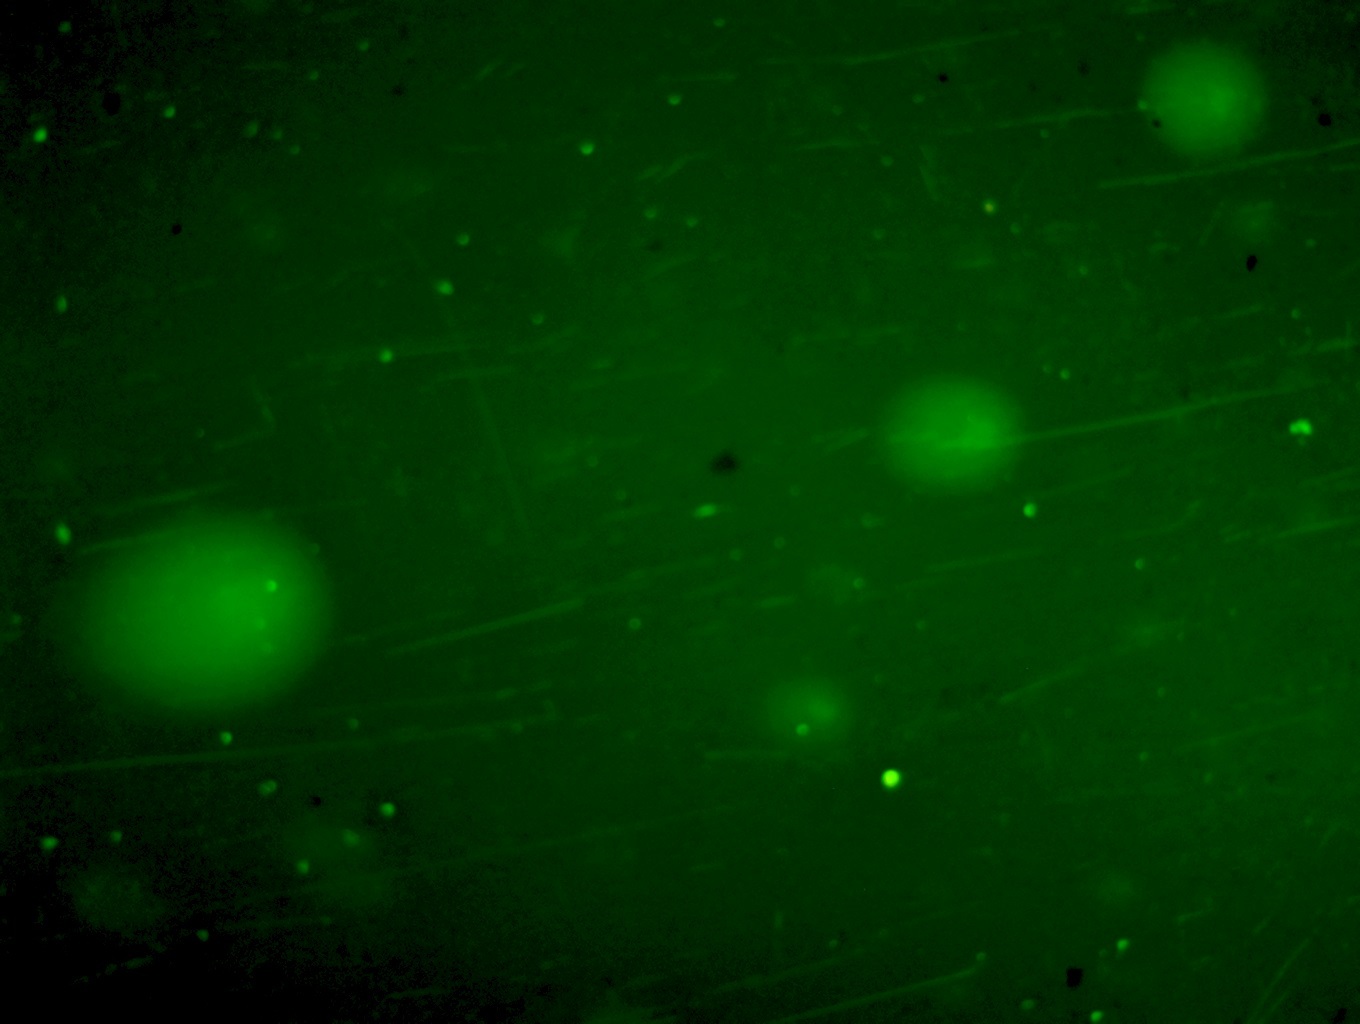

Введение. Проведена экспериментальная оценка влияния ССL4 и трансплантации клеток фетальной печени (КФП) на степень деградации и процессов репарации ДНК в клетках печени крыс, используя метод щелочного гель – электрофореза единичных клеток.

Материал и методы. Острое токсическое поражение печени крыс моделировали однократным внутрижелудочным введением крысам – самкам линии Вистар препарата CCl4 в масляном растворе в дозе 3000 мг/кг. В качестве протекционного средства использовали суспензию КФП плодов крысы 19 ДР. Для количественной оценки, степени повреждения ядерной ДНК клеток печени, применяли метод щелочного электрофореза единичных клеток (ДНК-комет) на 1, 3, 5, 7 и 16 сутки эксперимента.

Результаты. Внутривенное введение КФП через 6 часов после воздействия тетрахлорметана активировало процессы репарации ДНК в гепатоцитах крыс на 5 – 7 сутки, что приводило к снижению интенсивности повреждения ядерной ДНК. Тенденция к уменьшению числа неповрежденных гепатоцитов сохранялась и на 16 сутки эксперимента, при этом усиление репаративных процессов после введения КФП реализовалось в достоверном сокращении количества гепатоцитов с высокой интенсивностью повреждения ядерной ДНК.

Заключение. Использованный в наших экспериментах метод щелочного гель – электрофореза единичных клеток (ДНК-комет) позволил количественно оценить степень повреждения генома и его репарацию. Выявленные позитивные результаты свидетельствовали о протекторной роли КФП на структуру ДНК клеток печени крыс, после острого воздействия CCL4.